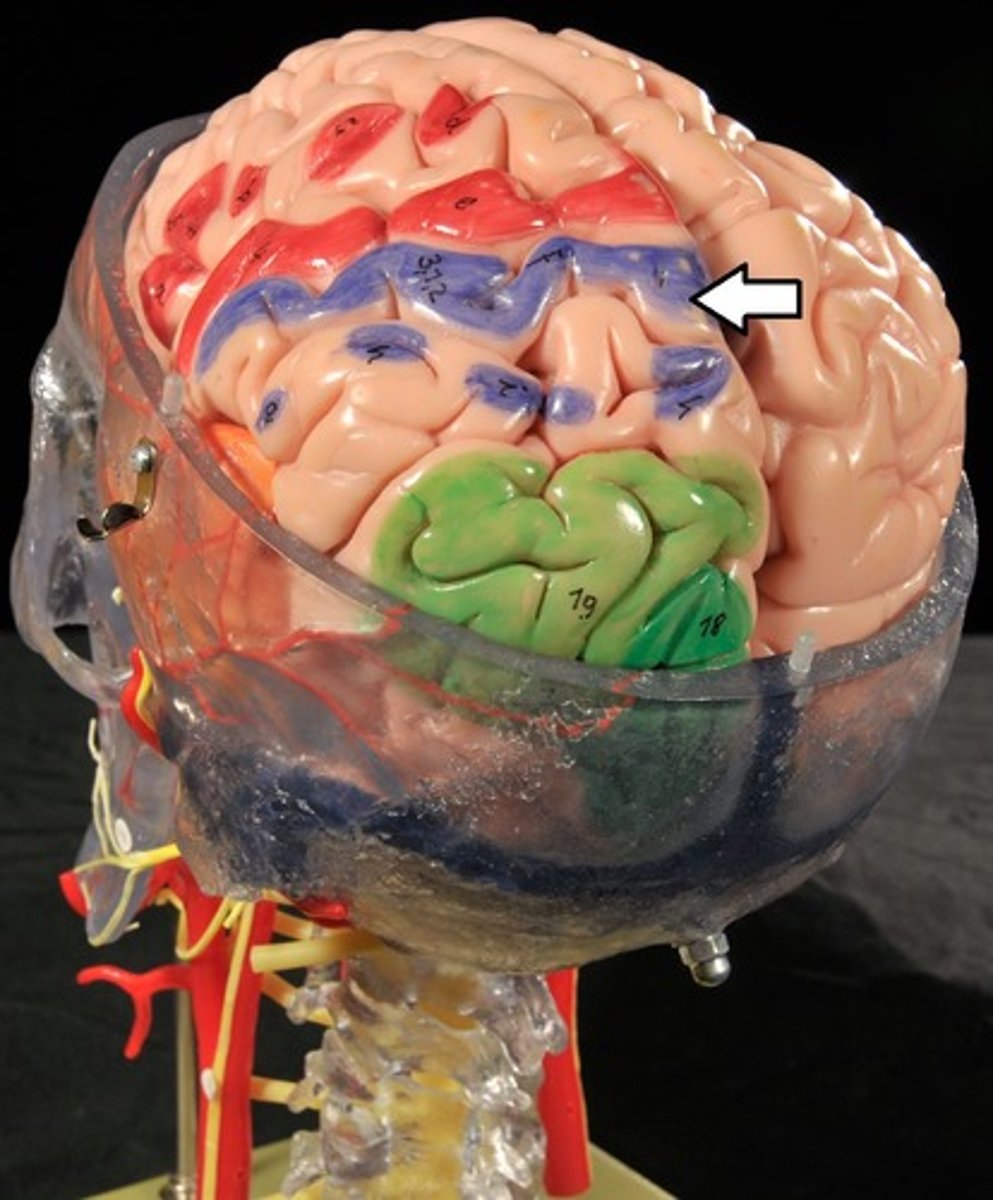

Parietal Lobe

Reception and evaluation (integration) of sensory information except for smell, hearing, and vision

Sensory Cortex

Sensory Interpretation and Association

Sensory Interpretation

Integrates sensory inputs (temp., pressure, etc.) to produce an understanding of what is being felt or observed (size, texture, etc.)

Association of sensory cortex

Links sensory inputs above to past memories to provide meaning to what we fell or see